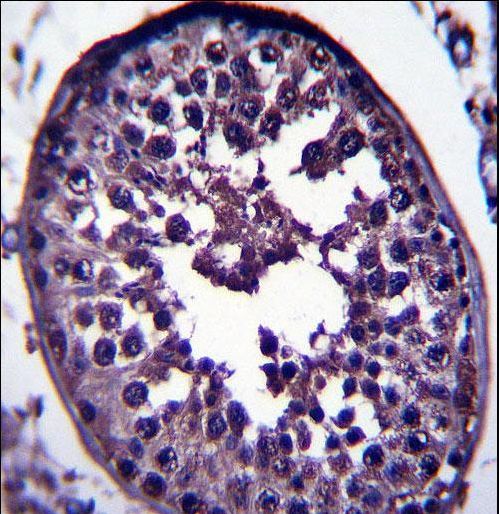

- Experimental details

- GAGE12H Antibody immunohistochemistry of formalin-fixed and paraffin-embedded human testis tissue followed by peroxidase-conjugated secondary antibody and DAB staining.